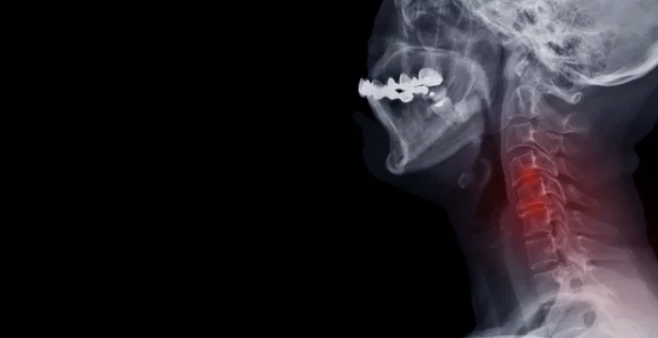

목디스크 질병에 대해 알아보겠습니다. 목디스크란 경추 추간판이 탈출되어 신경을 압박하여 증상을 유발하는 질환을 말합니다. 경추는 총 7개의 뼈로 구성되어 있으며, 뼈와 뼈 사이에는 충격을 흡수하는 역할을 하는 디스크가 있습니다. 오늘은 목디스크 증상 및 치료방법, 목디스크에 좋은 운동, 목디스크 수술 및 수술 후 회복기간 등 목디스크에 좋은 정보들을 알려드리겠습니다.

목디스크는 경추 뼈 사이의 디스크가 손상되어 신경을 압박하여 통증, 저림, 감각 이상 등의 증상을 유발하는 질환입니다. 목디스크는 주로 40~50대에 많이 발생하지만, 최근에는 스마트폰, 컴퓨터 사용이 증가하면서 20~30대에서도 발병률이 증가하고 있습니다.